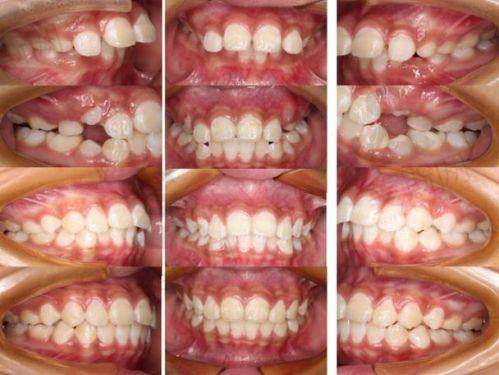

4. 隐形矫正:引进隐适美、时代天使等品牌,结合口扫技术3分钟出方案,矫正周期比传统托槽缩短30%。

7. 儿童早期干预矫正:针对3 - 12岁儿童乳牙期、替牙期错颌畸形,采用MRC肌功能矫治器,预防骨性畸形。

赵刚 正畸科主事:隐适美、时代天使认证医师,累计完成隐形矫正实例1500 +,擅长复杂牙列拥挤、骨性地包天矫正,创新“三维美学正畸”理念,兼顾牙齿排列与面部轮廓协调。

实例3:隐形矫正改变嘴凸问题

“我因为嘴凸一直特别自卑,在贝森口腔做了时代天使隐形矫正,赵刚主事根据我的面型设计方案,没拔牙就解决了问题。现在10个月,牙齿整齐了,侧脸线条也变好看了。矫正器特别隐形,同事都没发现我在整牙,太满意了!”——患者张女士(长治屯留区)